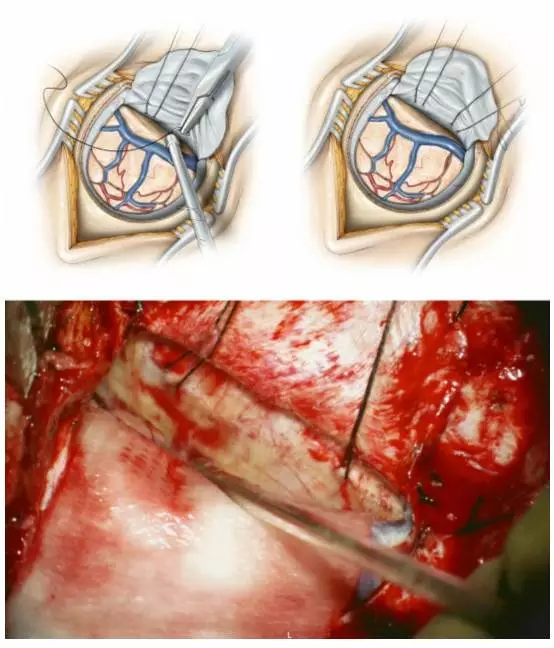

图9. 用两根缝线固定在大脑镰上端,轻轻牵拉上矢状窦,使其偏离中线。该法可直接扩大半球间的缝隙。将一片Telfa放置在正常大脑半球表面,起到保护作用。

图10. T形切开大脑镰,以暴露对侧大脑半球内侧面(楔前叶)。腰大池引流释放脑脊液,对于健侧半球移位,减小脑组织牵拉损伤至关重要。切口的下极要延伸到胼胝体水平,需电凝并横断下矢状窦。在导航下,定位和保护直窦以及其它相关的深部引流静脉。当大脑镰内的垂直切口接近直窦时,沿着从后向前的方向,以斜行方式完成。采用这个方法,翻开大脑镰时,楔前叶位于后方的区域才能得以暴露。

图11. 用缝线牵开大脑镰的硬膜瓣(小图),向对侧大脑半球(患侧)方向牵开,以增加到达同侧房部(健侧)的操作角度(上图)。相应的术中图片如下图所示,可暴露左侧楔前叶(吸引器尖端)。棉片保护健侧脑组织,以避免牵拉损伤。未使用固定牵开器。

图12. 图示为切除左侧巨大房部脑膜瘤后,楔前叶皮质切开的范围。一条牵开大脑镰硬膜瓣的缝线已经去除,以便更加清楚的展示手术通道。